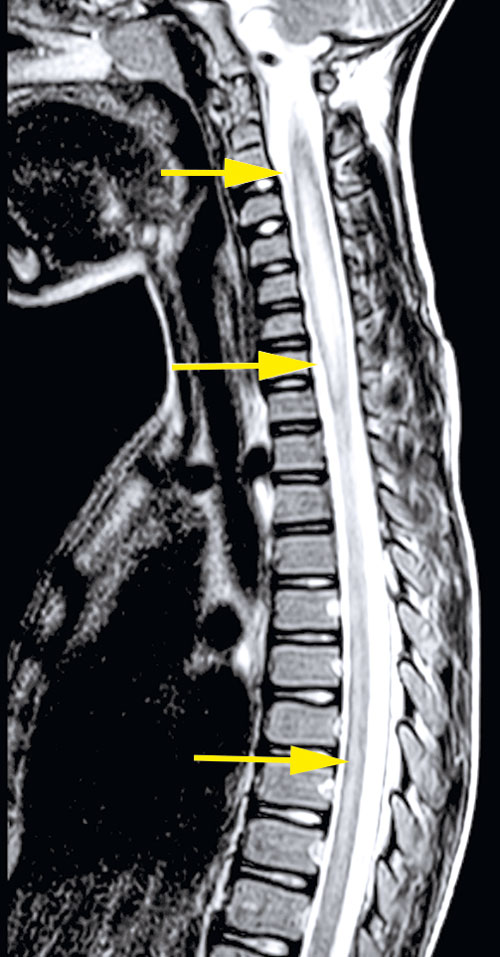

Omfattande mikrobiologisk utredning genomfördes, inklusive prov från likvor, blod, feces m m. Nasofarynxaspirat kontrollerades 10 dagar efter det att han först insjuknat och utföll positivt för enterovirus. Senare typning påvisade EV-D68. MR visade fokala signalförändringar i pons och medulla oblongata samt långsträckta signalförändringar över flera nivåer i ryggmärgens gråa substans utan kontrastmedelsupptag som vid en långsträckt central myelit (Figur 2).

Upprepad MR-undersökning efter drygt 2 veckor visade att signalförändringarna i ryggmärgen hade gått i regress men att det tillkommit kontrastupptag i cervikala och lumbala nervrötter (Figur 2). Neurofysiologiska undersökningar med EnEG, EMG och motoriska reaktionspotentialer 1 månad efter insjuknandet visade tecken på uttalad påverkan av nedre motorneuron i undersökta myotom på vänster sida och en generellt förlängd central överledningstid till undersökta segment på samma sida, vilket talade för påverkan även på centrala motoriska banor.

Figur 2 (fall 2). Vid initial MR-undersökning visade T2-viktad sekvens långsträckta signalförändringar i hela ryggmärgen (första bilden) samt fokalt i bakre delen av pons (andra bilden). Axialt i höjd med C2 påvisades engagerad grå substans (tredje bilden). Vid uppföljande MR-undersökning visade T1-viktad sekvens över halsryggmärgen (sista bilden) endast kontrastladdning i nervrötter.